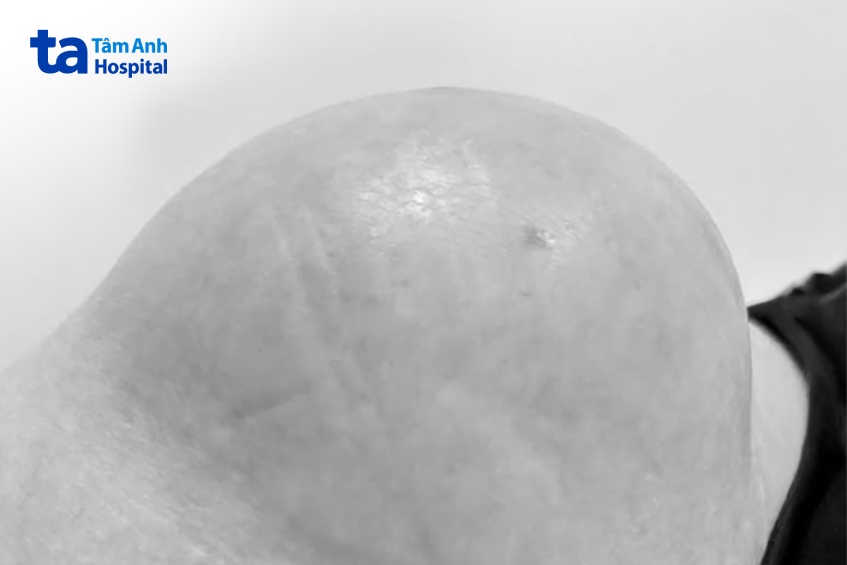

Bác sĩ CKI Lê Ngọc Vinh, Phòng khám Đa khoa Tâm Anh quận 7, nhận thấy da quanh u căng bóng, chiếm hết 1 bên mông. Kết quả siêu âm ghi nhận u bã đậu, lành tính, chèn ép thần kinh đùi. “Suốt 23 năm làm nghề, đây là lần đầu tiên tôi thấy u bã đậu khổng lồ như vậy” – bác sĩ Vinh nói.

Vùng mông chứa nhiều mạch máu và thần kinh từ chậu hông đi qua để xuống chân, ảnh hưởng các hoạt động của chân như đi, đứng, ngồi, co, duỗi… Bác sĩ Vinh khéo léo tách bó thần kinh ra khỏi u, sau đó dùng dao siêu âm cắt u, lấy trọn u ra khỏi mông chị H., hạn chế mất máu ở mức thấp nhất. Kết quả cân cho thấy u nặng hơn 2kg.

Thông thường bác sĩ đặt ống dẫn lưu để thoát dịch vết thương ra bên ngoài. U của chị H. có kích thước quá lớn, sau khi cắt để lại khuyết hổng tròn, có đường kính hơn 40cm, quá trình vết thương lành sẽ tiết lượng dịch rất lớn, không thể đặt ống dẫn lưu. Bác sĩ may vết thương, để lại lỗ nhỏ và chèn gạc lấp đầy khuyết hổng. Chị H. được xuất viện ngay trong ngày. Mỗi ngày, chị đến phòng khám để điều dưỡng vệ sinh, lấy gạc cũ thấm đầy dịch tiết và chèn gạc mới. Sau 2 tuần, vết thương của chị H. bắt đầu lành lặn.